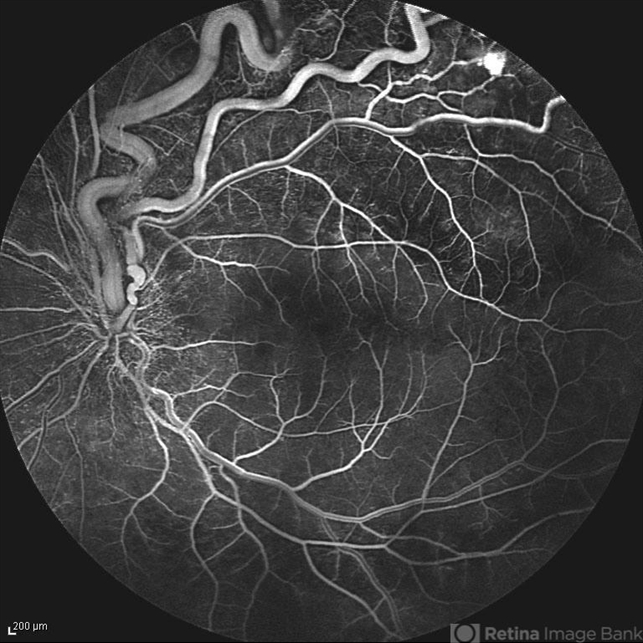

- Early FA image of the left eye of a 25-year-old woman with exudative retinal detachment secondary to retinal angiomatosis (Von Hippel-Lindau).